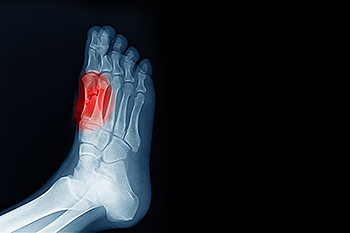

Broken Toes and the Role of a Podiatrist

A broken toe is commonly caused by trauma, such as stubbing the toe, dropping a heavy object, or sports injuries. Symptoms include pain, swelling, bruising, and difficulty walking or wearing shoes. In some cases, the toe may appear deformed. Risk factors include weak bones, high-impact activities, and poorly fitting footwear. If left untreated, a broken toe can lead to improper healing and long-term discomfort. A podiatrist can assess the severity of the fracture, provide appropriate treatment, prescribe protective footwear, and ensure proper healing. If you suspect a broken toe, it is suggested that you seek care from a podiatrist who can provide an accurate diagnosis and treatment..

What to Know About a Broken Toe

Although most people try to avoid foot trauma such as banging, stubbing, or dropping heavy objects on their feet, the unfortunate fact is that it is a common occurrence. Given the fact that toes are positioned in front of the feet, they typically sustain the brunt of such trauma. When trauma occurs to a toe, the result can be a painful break (fracture).

Severe toe fractures may be treated with a splint, cast, and in some cases, minor surgery. Due to its position and the pressure it endures with daily activity, future complications can occur if the big toe is not properly treated.